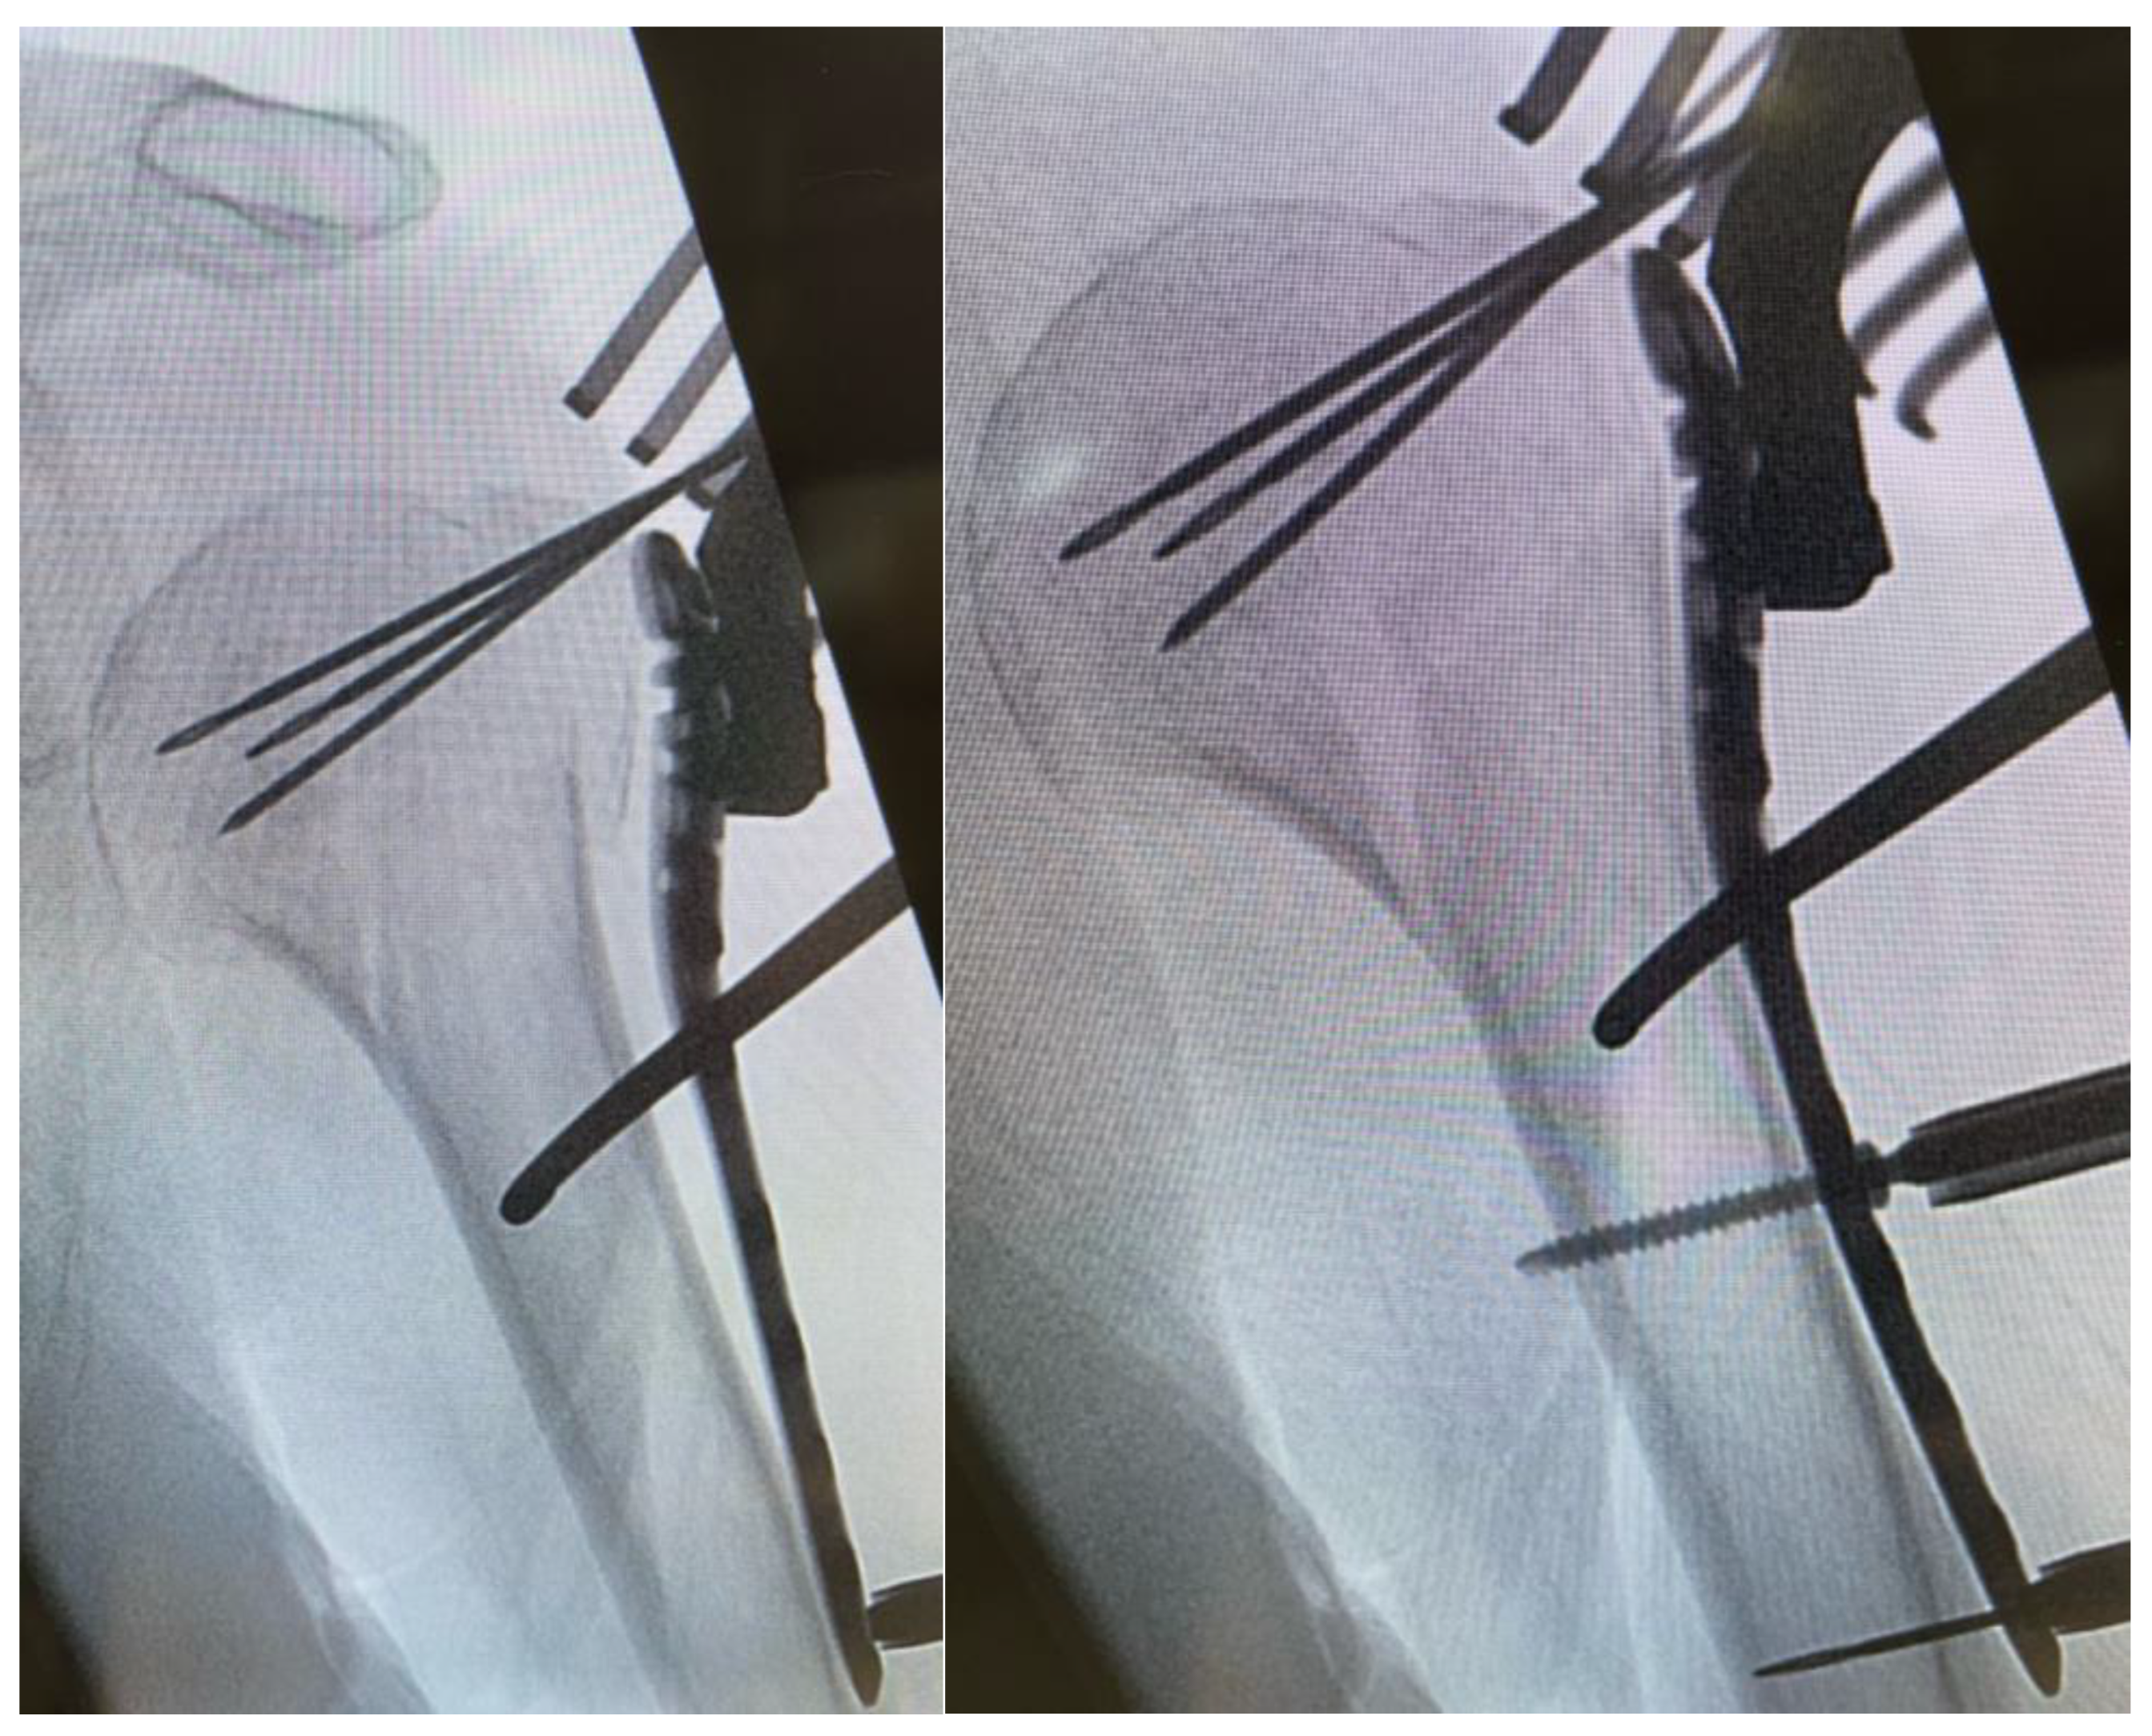

After fluoroscopic control of reduction and screw placement, a radiological contrast agent was injected prior to augmentation to prevent leakage into the joint. Afterwards, every screw was augmented with 0.5–1 mL of Traumacem V+ under fluoroscopic control (Figure 3).

Figure 3. Fluoroscopic control after cement augmentation of the screws.